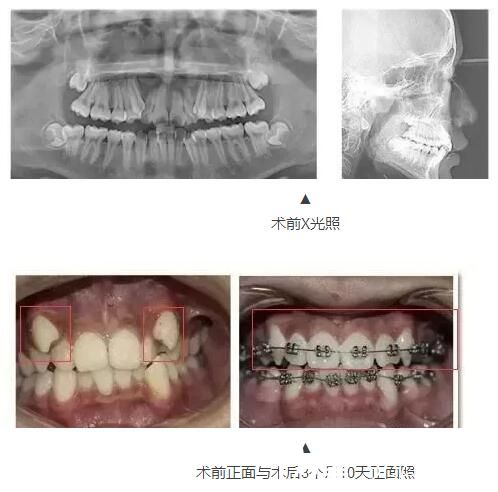

案例一:16岁中学生牙齿矫正

16岁中学生乐乐一直是老师眼里的好学生。然而让他头疼的是,由于自己以前的不良习惯,导致现在的牙齿不齐,甚至不敢开口露出牙齿。

三个月前,小斌通过朋友的推荐,来到泰州丽都医院,希望医生可以还他一口整齐的牙齿。医生给他制定了金属托槽矫治方案。小斌正式成为牙套族,但让他吃惊的是,三个月后他前来检查牙齿,牙齿已经发生了翻天覆地的变化!